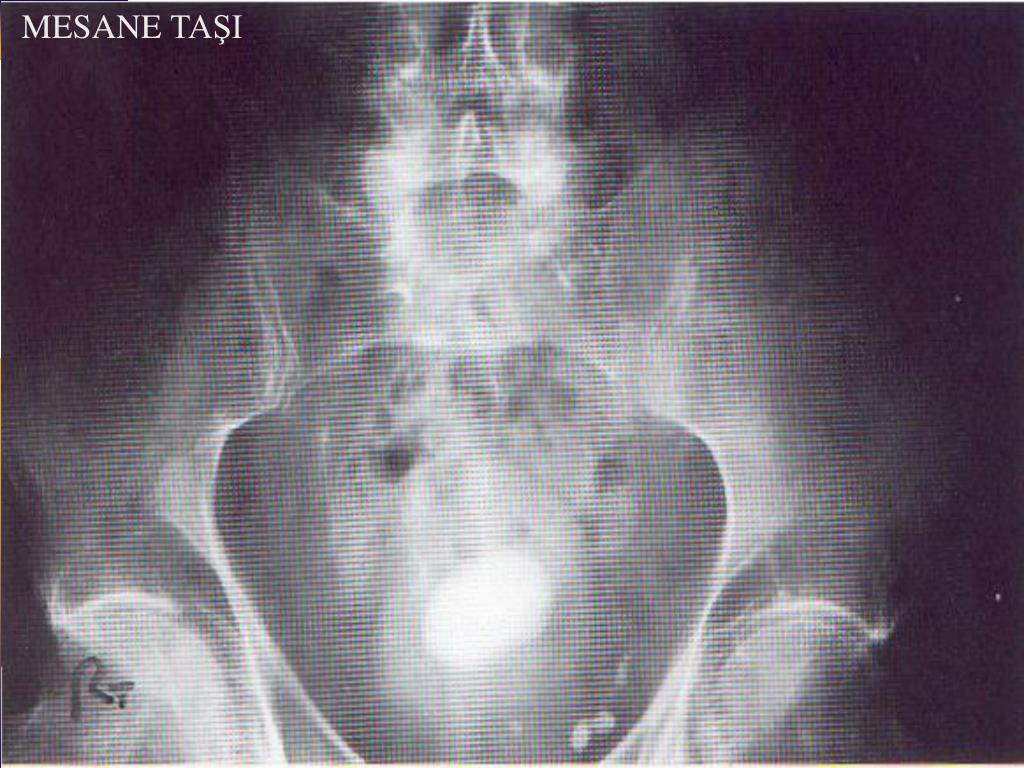

29. İntravenöz pyelografi (IVP) - Prostatik indentasyon - Balık oltası görünümü - Mesane taşı - Trabekülasyon artışı, sellüler ve divertiküller - Post- voiding grafide residüel idrar saptanması

31. MESANETAŞI